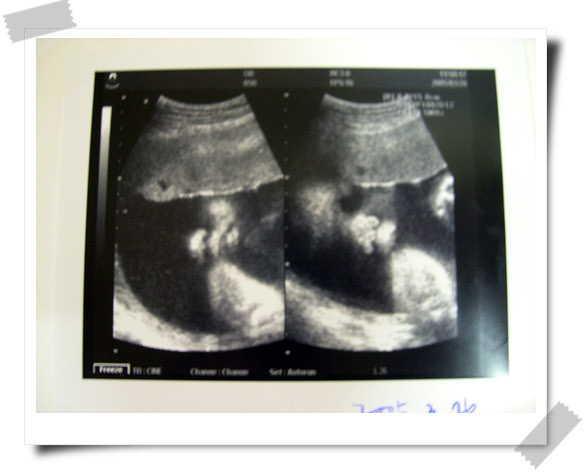

오늘은 짧게 초음파로만 널 만났단다.

2주후에 얼마나 컸는지 자세하게 알려준다는구나.